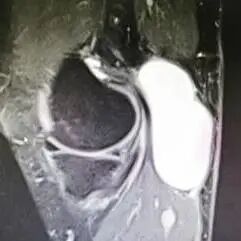

治疗关节囊肿的方法包括保守治疗和手术治疗。保守治疗包括使用非甾体类抗炎药、物理治疗和囊肿抽液等。手术治疗通常是在囊肿较大或症状严重的情况下进行,包括关节镜下囊肿切除和开放性手术切除等。传统的开放式手术:具有疤痕大、影响关节功能,由于没有处理膝关节腔内病变及后方关节囊的裂隙样结构,囊肿相对容易复发,病人恢复缓慢等缺点。关节镜手术可以做到切口小、恢复快,同时可以做到“标本兼治”,复发率低。如下图所示:

关节镜治疗腘窝囊肿方式有多种,常见的关节镜手术方式有:①囊外切除—双后入路,一般用于原发型囊肿;②后关节囊裂隙样结构缝合;③囊内切除—前外侧入路结合单后内侧入路;④囊内切除—双后内侧入路囊内切除术。

选择何种方式可依据术前核磁共振的检查情况决定。核磁共振显示腘窝囊肿与关节腔相通,腓肠肌间隔血管、神经的囊肿时建议的手术方式为前内外侧入路处理膝关节腔病变+单后内或双后内入路切除囊肿。如下图所示: